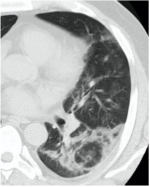

Методы лучевой диагностики применяют для выявления COVID-19 пневмоний, их осложнений, дифференциальной диагностики с другими заболеваниями легких, а также для определения степени выраженности и динамики изменений, оценки эффективности проводимой терапии.

К методам лучевой диагностики патологии ОГК пациентов с предполагаемой/установленной COVID-19 пневмонией относят:

- Компьютерную томографию легких (КТ),

КТ имеет высокую чувствительность в выявлении изменений в легких, характерных для COVID-19. Применение КТ целесообразно для первичной оценки состояния ОГК у пациентов с тяжелыми прогрессирующими формами заболевания, а также для дифференциальной диагностики выявленных изменений и оценки динамики процесса. КТ позволяет выявить характерные изменения в легких у пациентов с COVID-19 еще до появления положительных лабораторных тестов на инфекцию с помощью МАНК. В то же время, КТ выявляет изменения легких у значительного числа пациентов с бессимптомной и легкой формами заболевания, которым не требуется госпитализация. Результаты КТ в этих случаях не влияют на тактику лечения и прогноз заболевания при наличии лабораторного подтверждения COVID-19. Поэтому массовое применение КТ для скрининга асимптомных и легких форм болезни не рекомендуется.

6. Внутривенное контрастирование при КТ у пациентов с известной/предполагаемой вирусной (COVID-19) пневмонией проводится при подозрении на заболевания и патологические состояния, диагностика которых невозможна без использования контрастных средств (ТЭЛА, онкологические заболевания др.). Внезапный рост концентрации Д-димера в анализах крови и клиническое подозрение на ТЭЛА являются важными критериями для выполнения КТ-ангиопульмонографии при условии, что ее положительный результат может оказать влияние на лечение и ведение пациента.